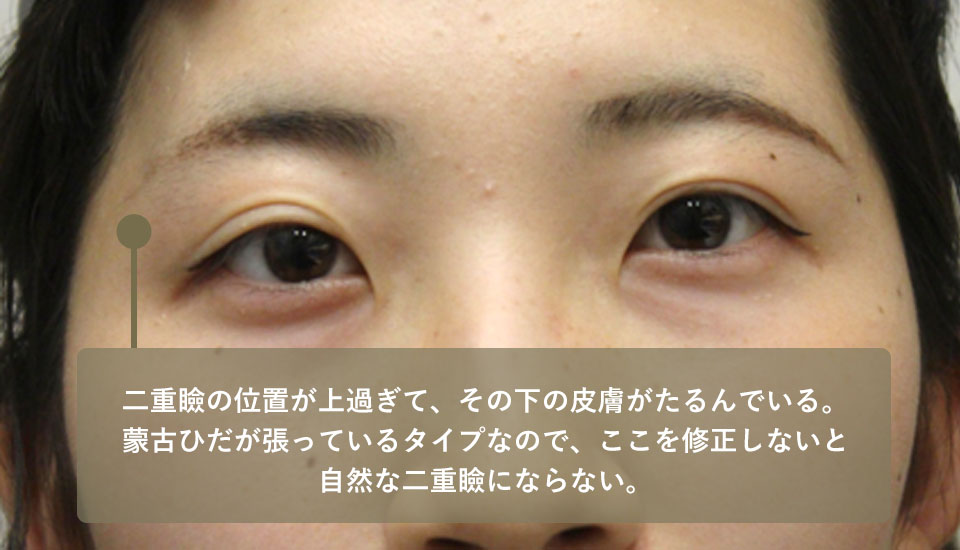

1年前に大手D美容外科で埋没法の手術を受けたが、術後に眼瞼の形状が不自然になってしまったので修正希望で来院。この方も症例2と同様に重瞼の位置が高すぎるので重瞼よりも下の皮膚がたるんでしまっています。

もう一つ、問題があります。それは内眼角贅皮という目頭の皮膚が張り出していることです。これは蒙古ひだともいわれるものでアジア人とくに東アジア人に多くみられるものです。

蒙古ひだが張ってしまっているので、いくら上眼瞼を綺麗に仕上げても、下に引っ張られてしまう以上、綺麗な重瞼線にはなりません。

このためこの方には内眥形成術(目頭切開)と上眼瞼の皮膚切除、重瞼作成を行いました。術後、平行型の綺麗な重瞼線が出来て表情も自然になりました。

| 術前 | 二重瞼の位置が上過ぎて結局その下の皮膚がたるんでいる蒙古ひだが張っているタイプなのでここを修正しないと自然な二重瞼にならない |

|---|---|